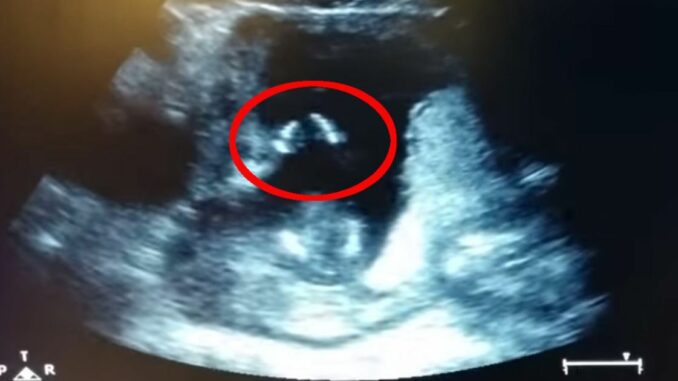

Manželé Jennifer a její manžel přišli s originálním způsobem, jak oznámit světu radostné očekávání svého prvního dítěte. Rozhodli se natočit video, ve kterém Jennifer zpívá známou píseň během ultrazvukového vyšetření. To, co se stalo následně, překonalo všechna jejich očekávání. Nejenže jejich miminko začalo v bříšku tleskat, ale video se stalo virálním hitem.

Co všechno se na tomto magickém ultrazvuku odhalilo naleznete v pokračování tohoto článku.